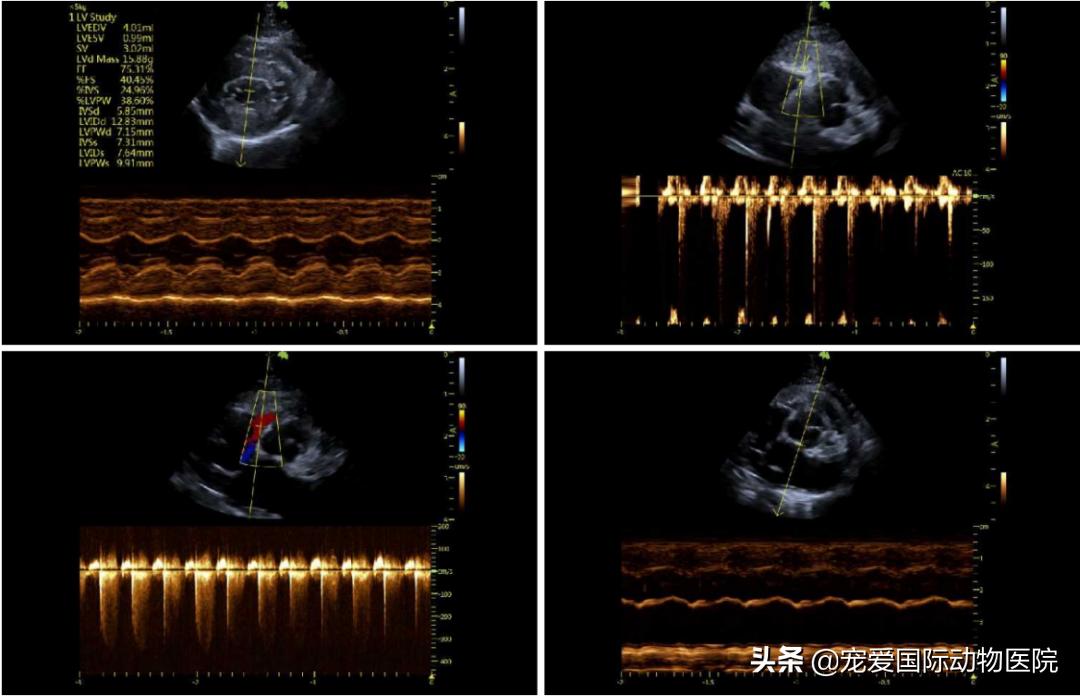

超声监测是目前最快、最有效的确诊方式之一,给猫咪做个心脏超声波检查的 超声心动图检查对肥厚性心肌病的诊断最敏感 。

彩超检查:提示

肥厚性心肌病与腹主动脉血栓

在腹主动脉超声中可见

腹主动脉终端血流信号消失